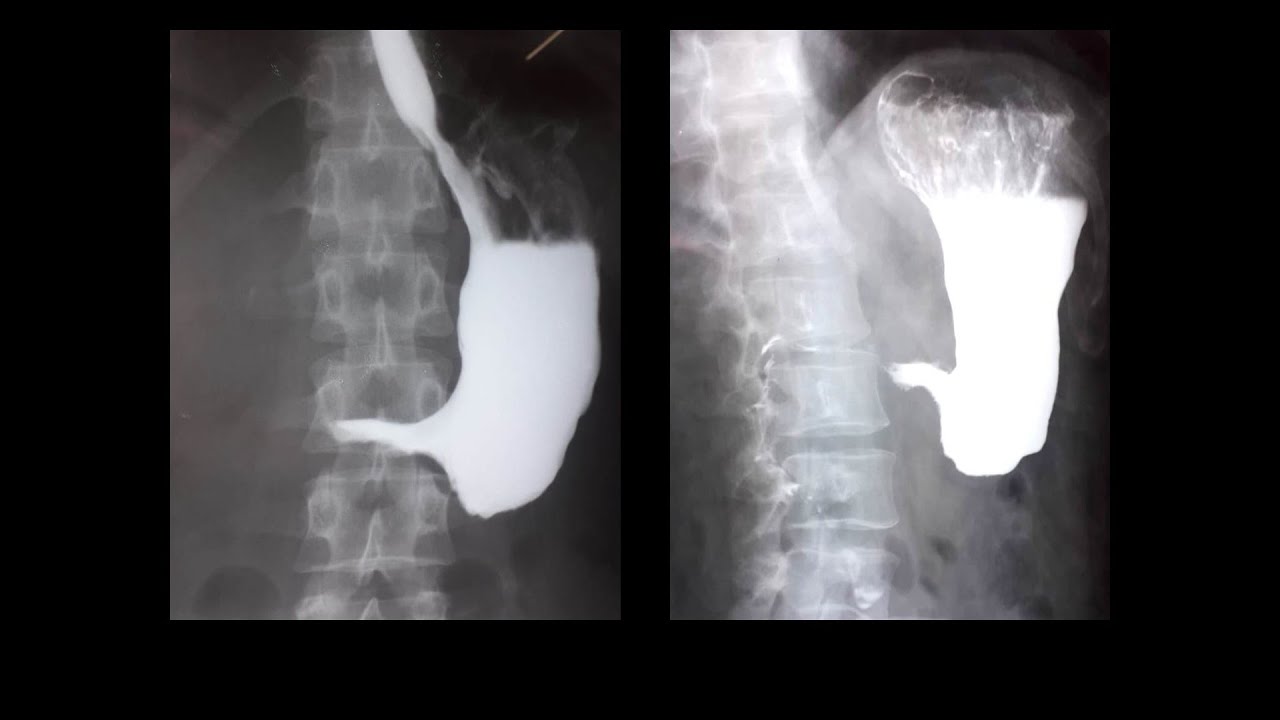

Лимфодиссекция желудка